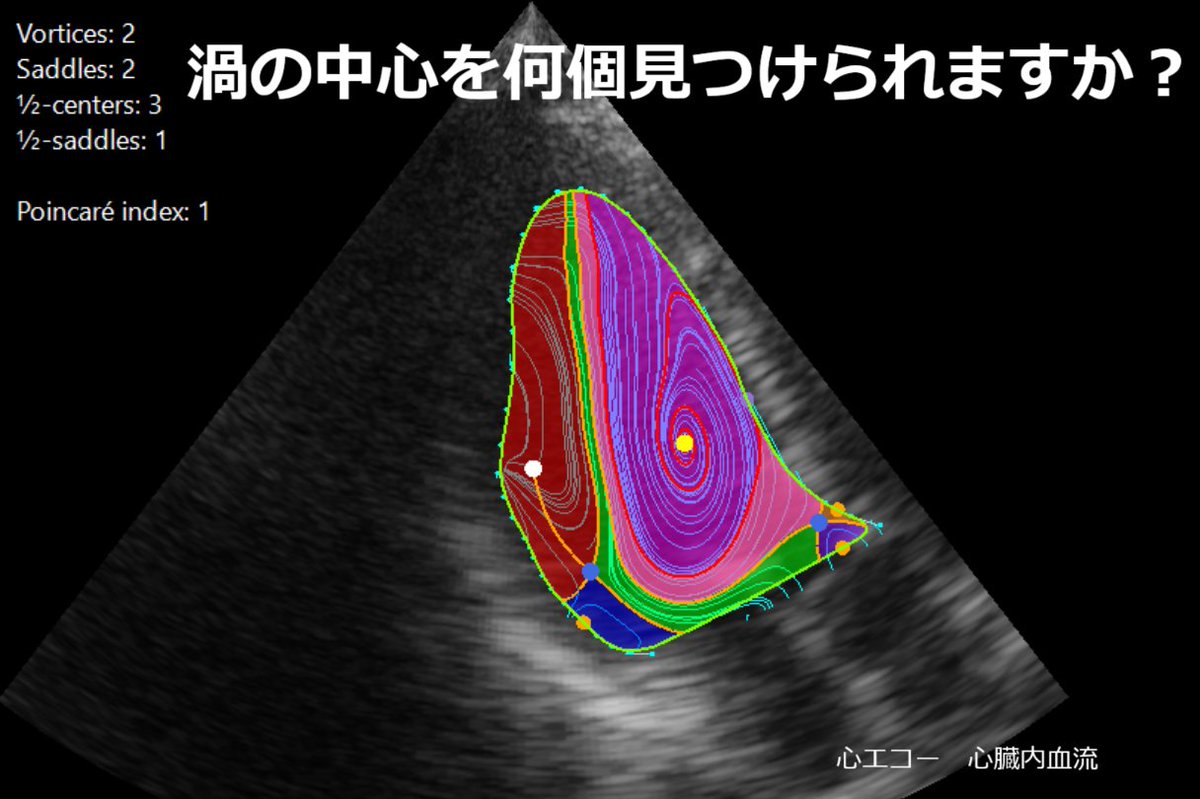

㊗️板谷先生 左室渦流🌊 #Topological 理論 🫀短時間範囲で収縮弛緩繰り返すため位相分類理論で想定の滑り境界条件満たしていない👉n-bundled ss-saddle縮退特異点導入👉🌊構造トポロジカル渦構造識別に成功🎉非効率血流パターン #Energyloss 可視化成功🎉🎉🎉 キャ~😆

渦の中心を何個発見できますか? 心臓内の『渦血流』を同定する理論を世界に先駆けて構築:心血流の渦のパターンを文字化し、早期に心不全を発見する可能性 jst.go.jp/pr/announce/20… #心臓は血流で診断する時代へ #血流解析 #VFM #カーディオフローデザイン #心エコー #心不全 #早期発見

CFD_Inc's tweet image. 渦の中心を何個発見できますか?

心臓内の『渦血流』を同定する理論を世界に先駆けて構築:心血流の渦のパターンを文字化し、早期に心不全を発見する可能性